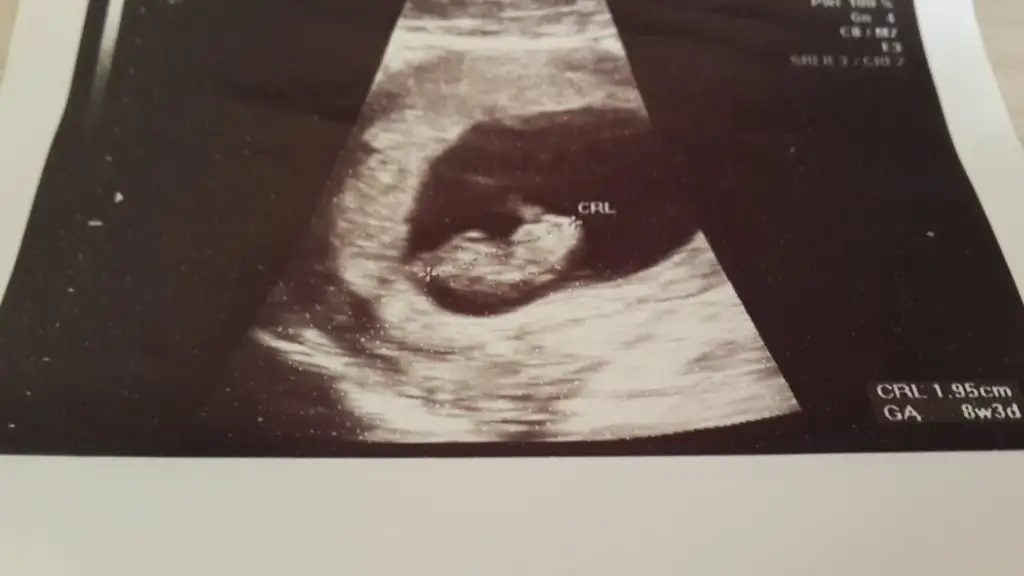

bu bizim 13 haftalık fotomuz.şimdi 32 haftalığız.hep çeşitli doktorlara gittim 20 haftalıkken %99 kız dediler.diğer doktorlar da sana söylenmiştr zaten cinsiyeti dediler.bana öyle geliyorki tam bakmıyorlar.onlar da kız dedi.ama ben erkek hissediyorum ve kime sorsam erkek dedi bu fotoya ve benm karın yapıma göre.yüzük testinde de erkek çıkıyo.ya bilmiyorum bakalım

Daha belli olmadımı ki senin ??? Kız mi erkek mi epey li zamanda geçmiş. Erkek mi diyorsun canım sende. Kız da deniyor erkek te. Nasıl anliyorsunuz????hangi fotodan anladin.ben bakıyorum bişey goremiyorum. doktora haftaya gitcem daha bişey söylemediler.